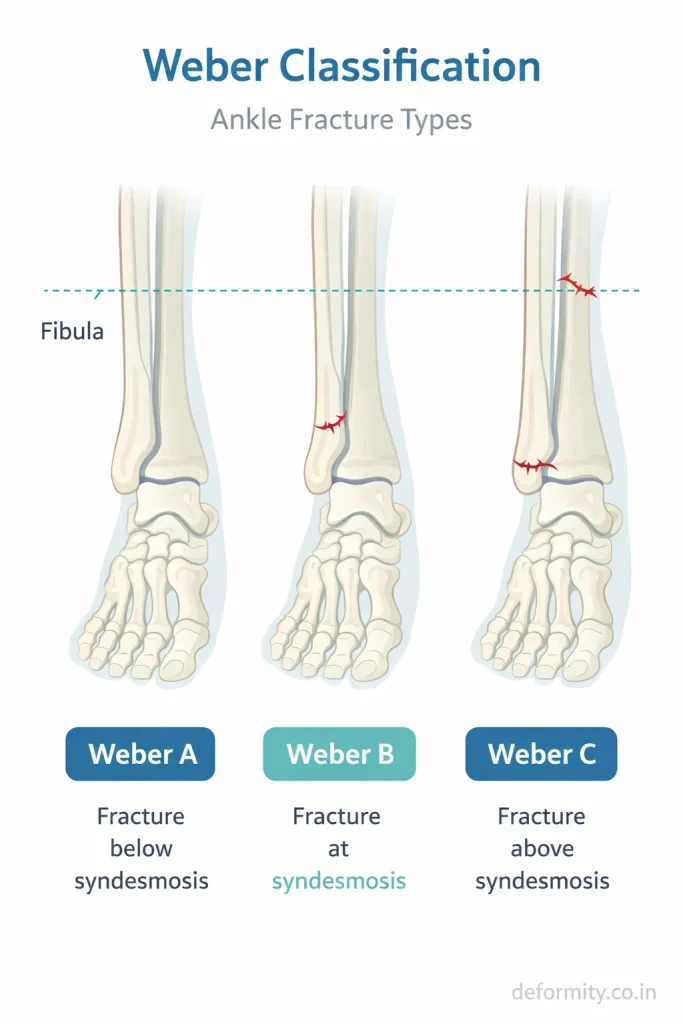

These forces can cause a fracture at different levels of the fibula, which is why classification systems like the Weber classification are important.

Lateral malleolus fractures vary in pattern and stability. The treatment depends heavily on the fracture type.

Weber A Fracture

Fracture below the syndesmosis. Usually stable and treated without surgery.

Weber B Fracture

Fracture at the level of the syndesmosis. Stability varies and requires careful assessment. Some cases need surgery.

Weber C Fracture

Fracture above the syndesmosis. Usually unstable and associated with ligament injury. Surgery is often required.